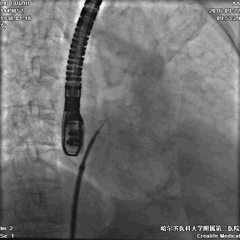

手术过程—全麻下食道超声结合DSA指导房间隔穿刺

穿刺点选择中间略偏后下位。

穿间隔后,给予肝素7000u,测得左房压力12mmHg。